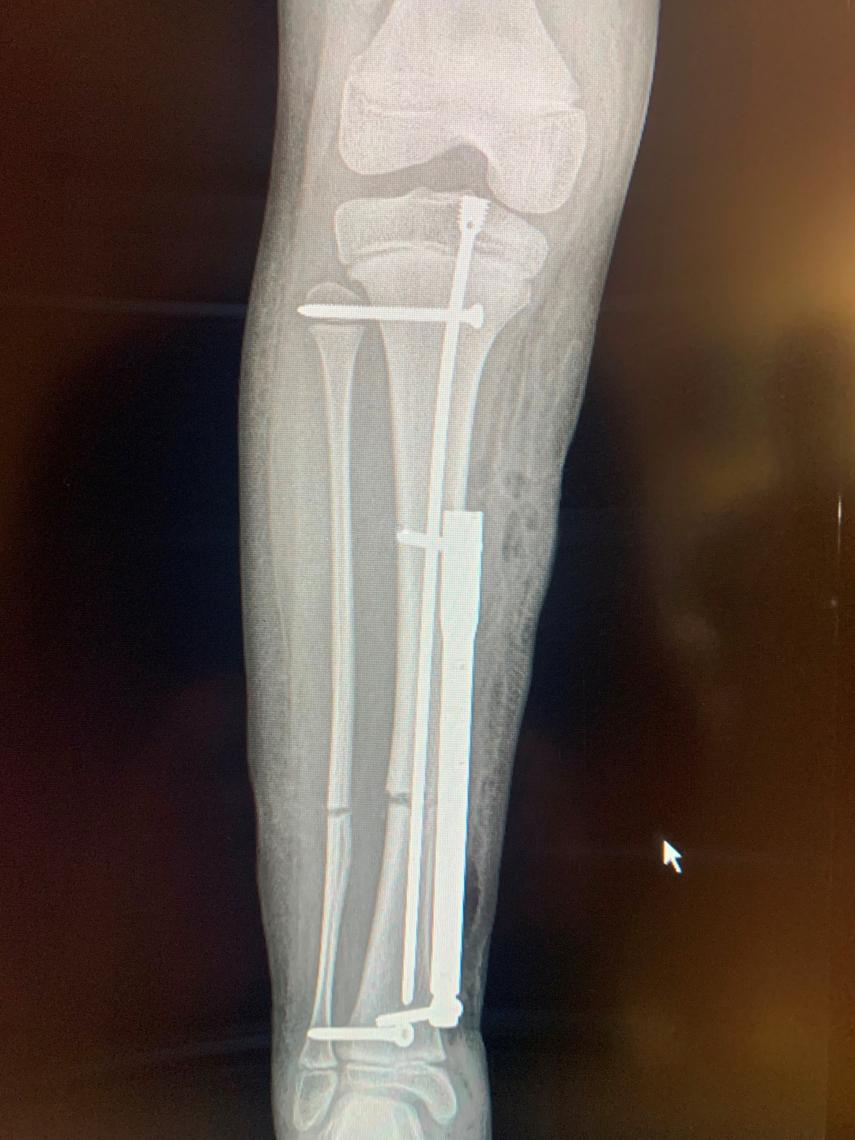

El dispositivo se fija en el exterior del hueso.

La nueva técnica, tal como detalla el especialista, consiste en la introducción de “una guía en el interior de la tibia, se corta el hueso y a través de una pequeña incisión a la altura del tobillo se introduce el dispositivo y se fija al hueso con tornillos”, aclara el doctor Downey. De esta manera, el dispositivo queda adosado al hueso, no dentro de él. Se usa un clavo “como si fuera un fijador externo pero por debajo de la piel, pero con mayor beneficio para el paciente porque no le estoy destruyendo la placa de crecimiento y sin necesidad de llevar ningún dispositivo por fuera”.